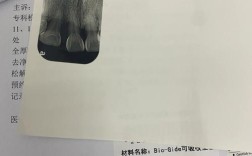

- 影像学检查: CBCT(锥形束CT)是必须的! 精确评估骨吸收的程度、范围、剩余骨量、重要解剖结构位置(神经管、上颌窦),可能需要取研究模型。

- 确定是否需要骨增量、采用哪种技术、骨增量与种植植入的时机(同期或分期)、选择何种种植体和修复方案。

- 骨愈合期: 这是最关键也最需要耐心的时期,通常需要4-9个月不等,具体取决于骨缺损大小、移植材料类型、患者自身条件,期间需定期复查。

- 精准的术前评估(尤其是CBCT)。